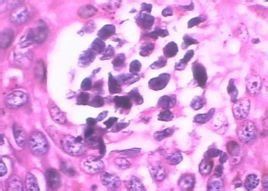

專家認為特異性陰道炎是由葡萄菌、鏈球菌、大腸桿菌及陰道嗜血桿菌等引起的陰道發炎。往往在陰道損傷、陰道內有子宮托或陰道塞、遺留棉球等異物,以及塗抹腐蝕性藥物、避孕用具或油膏、刺激性陰道沖洗等情況下,或因盆腔炎、附屬檔案炎、子宮內膜炎、流產及分娩子宮分泌物增多,長期子宮出血或陰道手術損傷等原因,使陰道的政策防禦功能遭到破壞,為病菌的生長繁殖創造條件而發生特異性陰道炎。